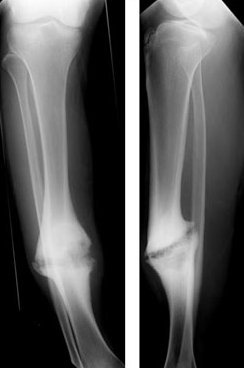

Fractures can range from simple cracks to severe, complicated breaks that affect multiple bones and tissues. Complex fractures often require advanced surgical expertise and specialized care to restore proper bone alignment, mobility, and function. With modern orthopedic techniques, patients can achieve full recovery and return to daily life with confidence.